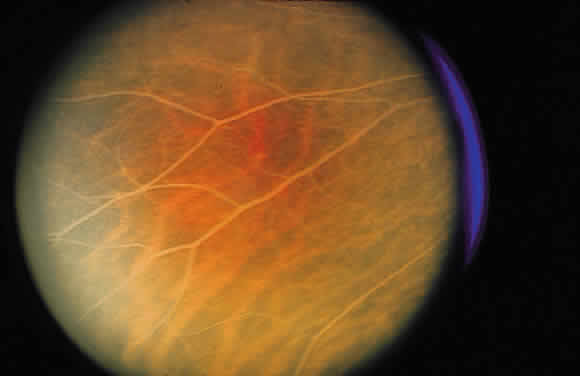

for the detection of microaneurysms than is direct fundus observation.18  Fig. 52. A. Fundus photograph of nonproliferative diabetic retinopathy. Notice the

dilated veins, the small exudate clusters, the ischemic infarct (cotton-wool

spot), and the numerous microaneurysms and small hemorrhages. B. Mid-venous phase fluorescein angiogram of the same eye. Notice the focal

area of nonperfusion in the superior temporal arcade (ischemic areas), the

fluorescing microaneurysms, and the hemorrhages, which appear

dark in contrast to the background fluorescence. (Courtesy of William Tasman, MD, Philadelphia, PA) Fig. 52. A. Fundus photograph of nonproliferative diabetic retinopathy. Notice the

dilated veins, the small exudate clusters, the ischemic infarct (cotton-wool

spot), and the numerous microaneurysms and small hemorrhages. B. Mid-venous phase fluorescein angiogram of the same eye. Notice the focal

area of nonperfusion in the superior temporal arcade (ischemic areas), the

fluorescing microaneurysms, and the hemorrhages, which appear

dark in contrast to the background fluorescence. (Courtesy of William Tasman, MD, Philadelphia, PA)